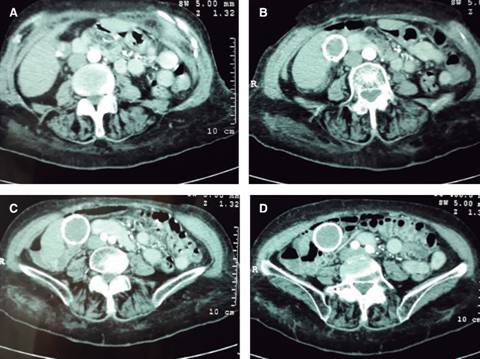

Figura 4: Tomografía computarizada de abdomen con doble contraste, en cortes axiales mostrando: en (A), polo superior de vesícula calcificada; en (B), cuerpo vesicular proximal a nivel de L4/L5; en (C), cuerpo vesicular a nivel de crestas iliacas; en (D), polo distal de vesícula biliar a nivel de L5/S1 a nivel intrapélvico, en paciente nonagenaria.